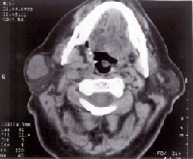

El diagnostico clínico se completa con la punción aspiración que nos da el diagnostico y la tomografía axial computerizada que nos define su extensión y relaciones de vecindad. El tratamiento es quirúrgico y siempre precisa un abordaje tipo paratiroidectomía, identificando el nervio facial a su salida del agujero estilomastoideo, siguiéndolo hasta sus ramas terminales, si la lesión se limita al lóbulo superficial, se practica una parotidectomía suprafacial o de lóbulo superficial, pero si el tumor afecta al lóbulo profundo, precisaremos parotidectomía total, debiendo siempre respetar el nervio facial. La lesión que afecta a la glándula submaxilar se le debe escindir en su totalidad incluyendo el tumor preservando la rama mandibular del facial. La recidiva de estas lesiones suele ser debida a resección insuficiente, debiendo incluir en la segunda amplios márgenes de tejido, para prevenir recidivas adicionales, en estos pacientes puede ser inevitable sacrificar ramas del nervio facial, en determinados casos está indicada la sutura o el injerto nervioso.

Adenoma Pleomorfo de Parótida, observamos claramente el parénquima parotídeo normal y el tumor mixto ( blanco) que abulta en el subcutáneo